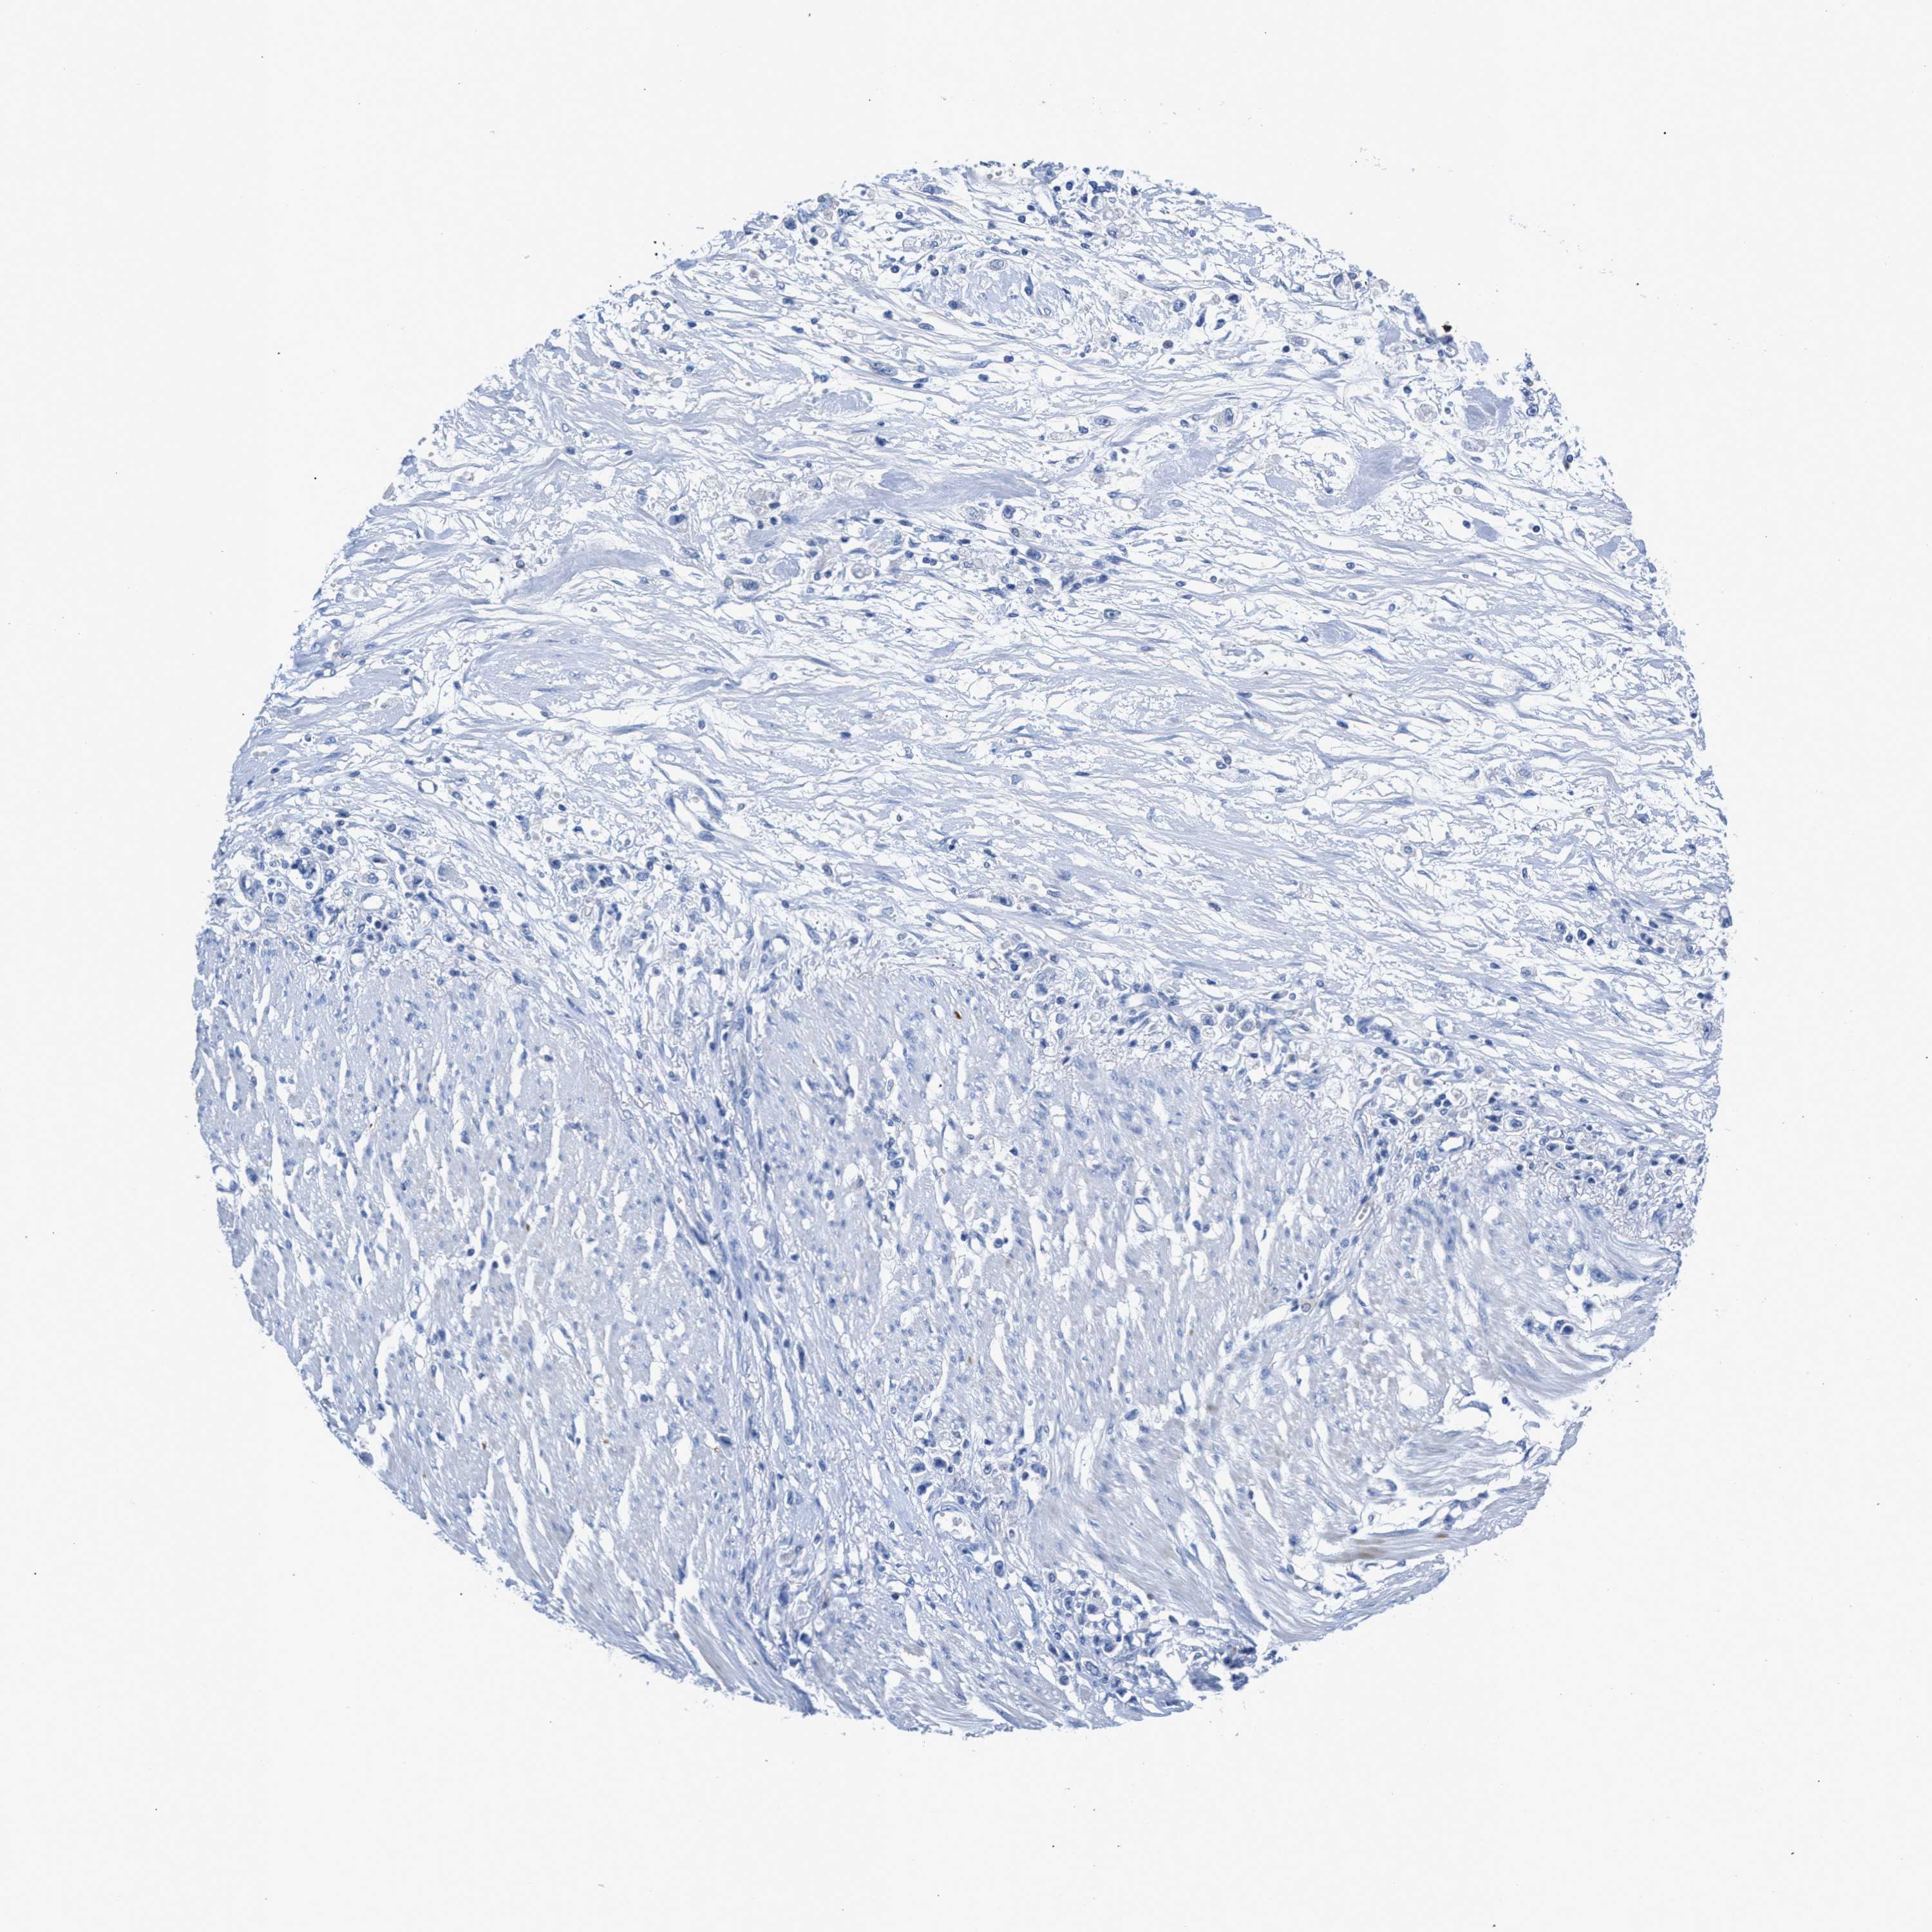

STOMACH CANCER - Protein expressioni

A mouse-over function shows sample information and annotation data. Click on an image to view it in a full screen mode. Samples can be filtered based on level of antibody staining by selecting one or several of the following categories: high, medium, low and not detected. The assay and annotation is described here.

Note that samples used for immunohistochemistry by the Human Protein Atlas do not correspond to samples in the TCGA dataset.

Antibody stainingi

Antibody staining in the annotated cell types in the current human tissue is reported as not detected, low, medium, or high, based on conventional immunohistochemistry profiling in selected tissues. This score is based on the combination of the staining intensity and fraction of stained cells.

Each image is clickable and will lead to virtual microscopy that enables deeper exploration of all samples and also displays staining intensity scores, fraction scores and subcellular localization as well as patient and tissue information for each sample.

Antibody HPA022532

Antibody HPA023064

Staining

High

Medium

Low

Not detected

Intensity

Strong

Moderate

Weak

Negative

Quantity

>75%

75%-25%

<25%

None

Location

Nuclear

Cytoplasmic/membranous

Cytoplasmic/membranous,nuclear

Adenocarcinoma, NOS